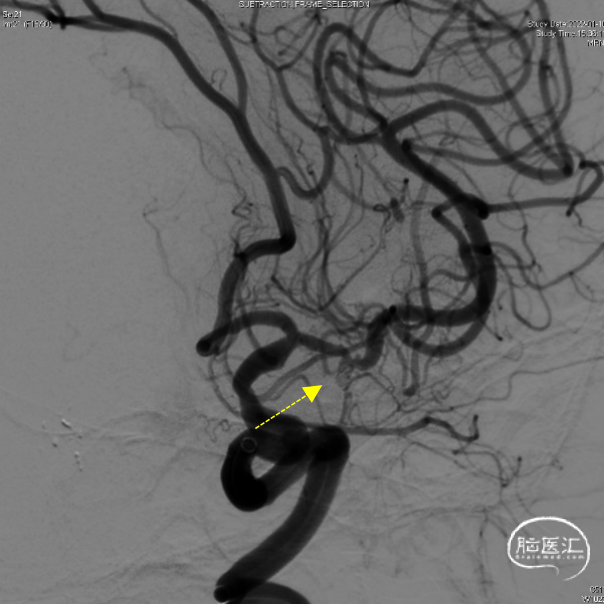

造影显示:颈内动脉迂曲,动脉瘤大小3.9×2.2mm,动脉瘤侧壁有边支发出,远端延续为较粗的向颞叶供血动脉(红色虚线)。

该患者颈内动脉迂曲,使用6F通桥银蛇DA远端通路导引导管(105cm),在0.035”超滑导丝配合下顺利到达岩骨段后继续送银蛇DA至海绵窦段,以便为手术提供有力支撑

6F通桥银蛇DA远端通路导引导管到位后,工作角度微导管抵近造影,证实动脉瘤侧壁发出的边支向颞叶供血。

动脉瘤大部填塞后,边支动脉血流完好。